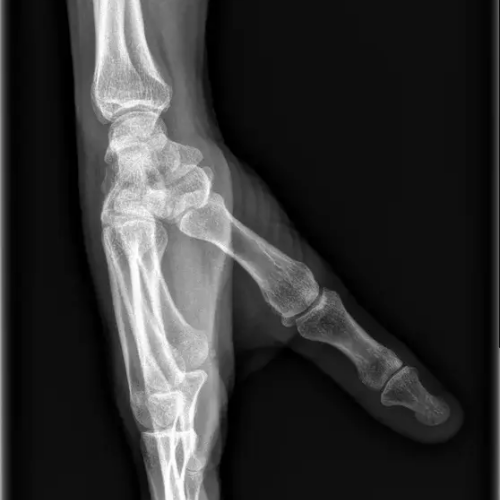

- fractures